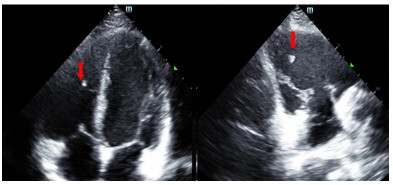

患者入院后无胸闷气促等不适主诉。入科查体:体温36.5 ℃,脉搏86次/min,呼吸频率16次/min,血压106/54 mmHg(1 mmHg=0.133 kPa),指尖氧饱和度99%~100%(未吸氧情况下),神清,瞳孔等大等圆,对光反射可,双肺呼吸音清,无明显干湿啰音,听诊心脏,律齐,无病理性杂音,左侧前臂近端及远端各一创面包扎,敷料干燥,未见明显渗出,左上肢肌力无法配合(考虑臂丛阻滞麻醉未完全恢复),余四肢肌力肌张力感觉无明显异常。立即完善相关检查(图 3、4),通过X线以及CT定位异物,超声评估异物在心脏中的活动情况及与心脏搏动时与瓣膜以及周围组织结构关系,可见异物在心脏内较固定,未影响瓣膜运动。同时血化验(动脉血气、感染指标、心肌酶谱、肌钙蛋白、D二聚体等)及心电图未见明显异常,请心胸外科会诊后建议暂予以抗炎保守对症处理。

| 图 3 外伤后第三次评估异物情况肺部CT检查图像 |